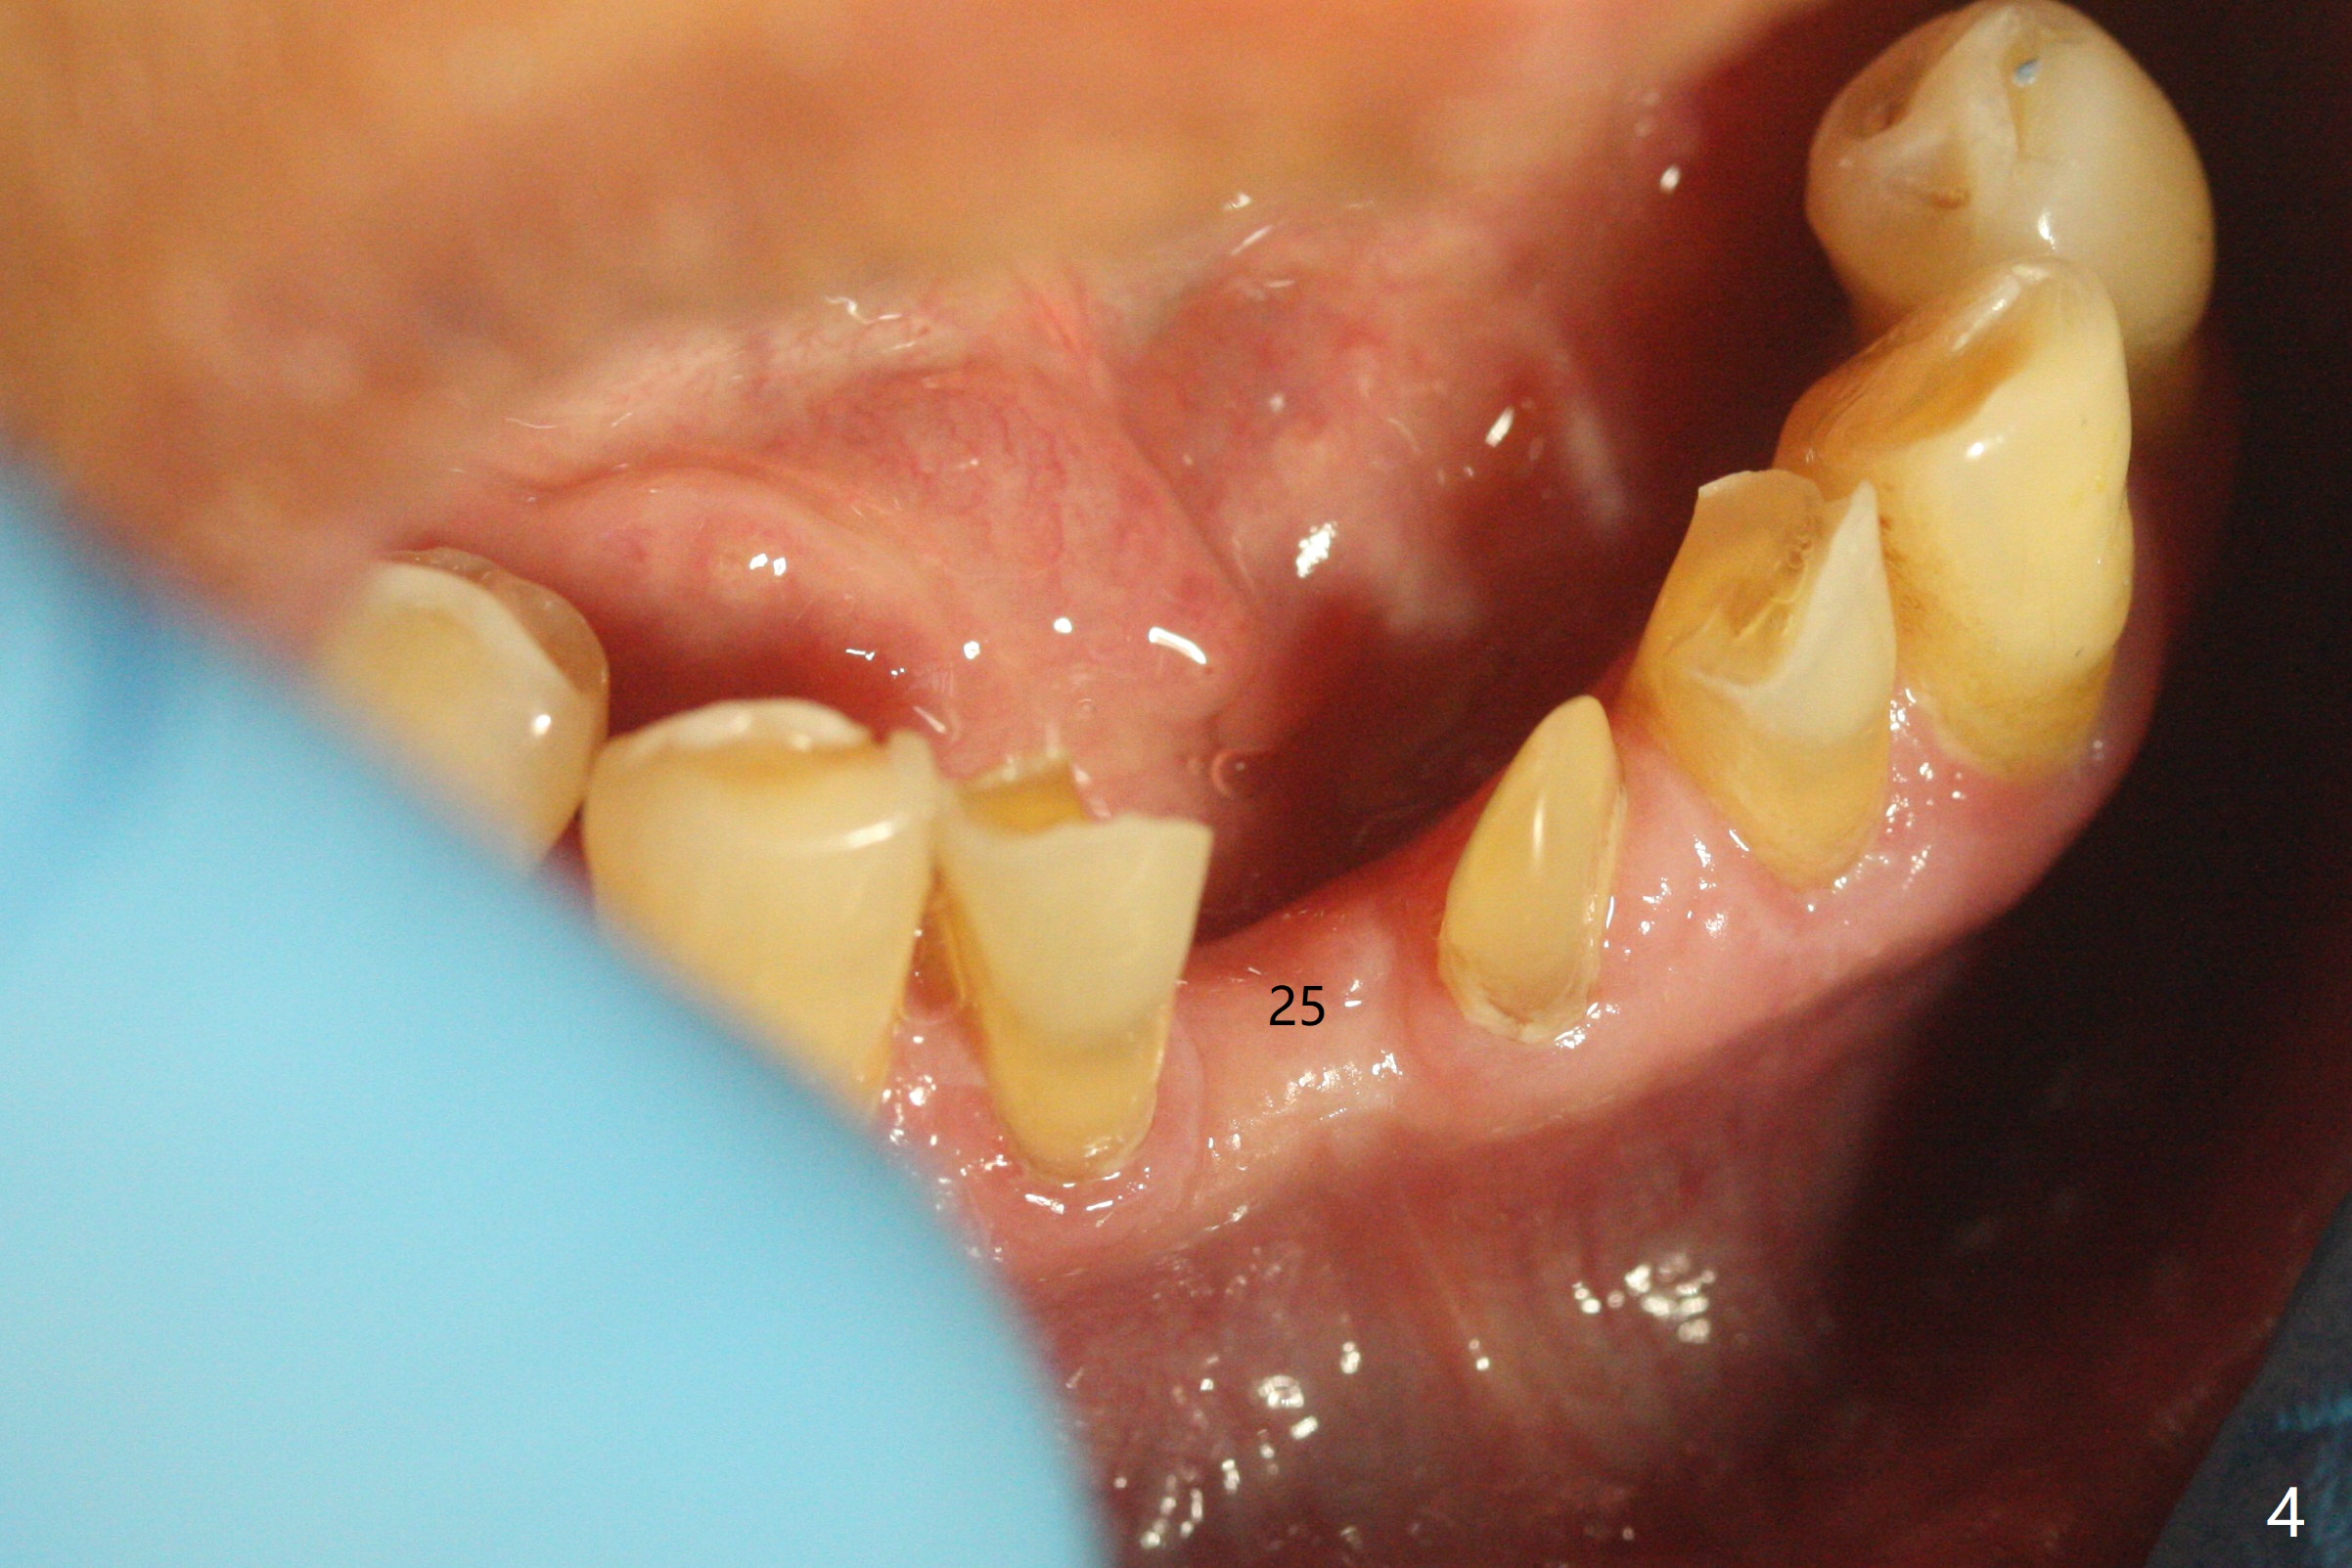

左下第一磨牙(#19)牙槽嵴狭窄,2.2毫米钻头完成导板钻洞后,舌侧骨板开始破裂(图一:<),打消牙槽嵴劈开术念头,放置2.5x8.5毫米一段式植体(图二(8.5毫米是最短植体)),好像离下齿槽神经管还有一定距离,适当植入深些(图四:箭头,15Ncm)。右下中切牙缺牙区牙槽嵴也十分狭窄(图四),最后不得不徒手植入2x8.5毫米植体(图五,六,25Ncm)。如果按设计植入2x12毫米植体,颊侧,或者舌侧骨板更容易穿孔。术后3.5月牙槽嵴下降(图七:箭头),可能术中那里压力太大,今后牙槽嵴钻洞要大。24号牙根尖阴影(图七),完成根管治疗(图八)。19牙位牙槽嵴吸收也严重(图九)。其实术后4个月19牙位牙槽嵴吸收并不严重(图十一)。